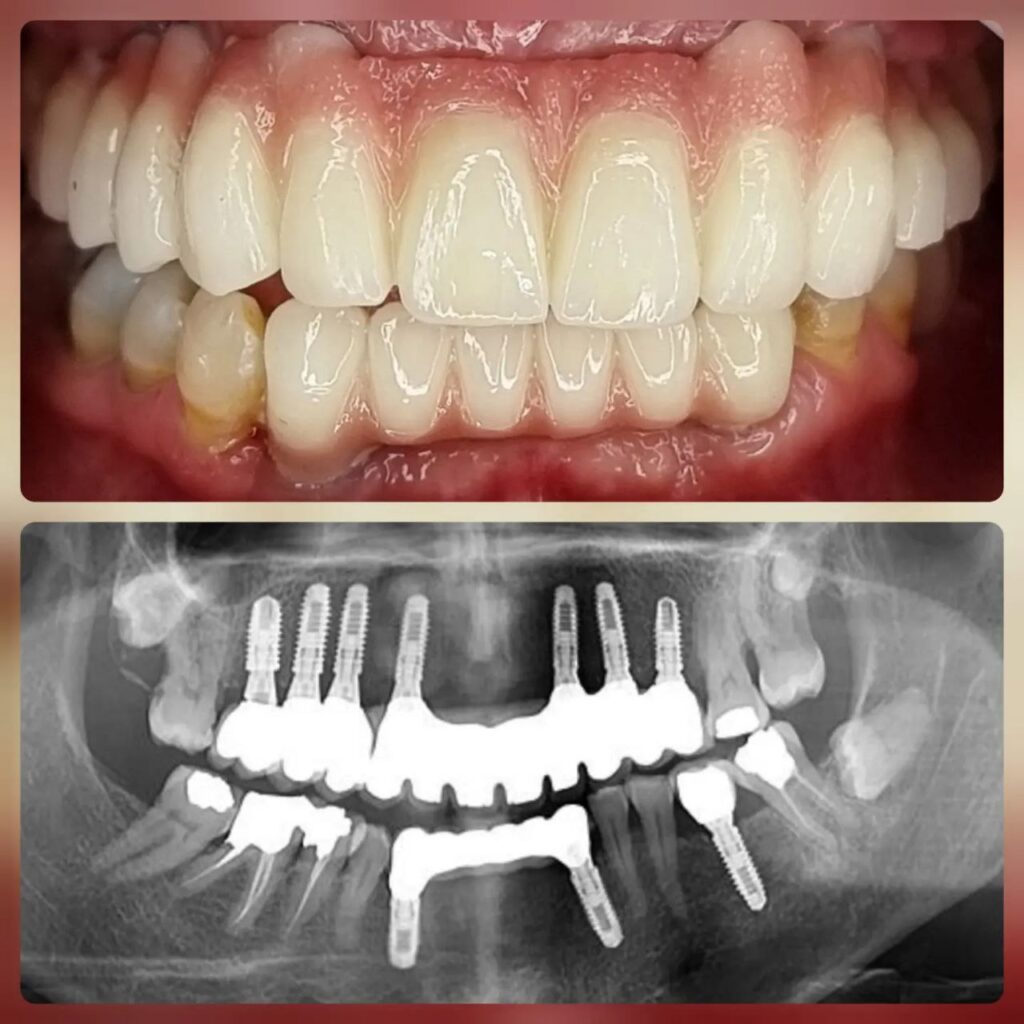

کاشت ایمپلنت دندان

اطمینان حاصل کردن از اینکه دندانهایتان به نحوی زیبا و طبیعی جایگزین شدهاند، از اهمیت بسیاری برخوردار است. ایمپلنت دندان به عنوان یک روش درمانی دائمی در دندانپزشکی شناخته میشود که حاصل آن، یک دندان زیبا و طبیعی در دهان شما خواهد بود.

هرچند که این روش درمانی هزینهی بیشتری نسبت به روشهای دیگر دارد، اما ارزش زیبایی که ایجاد میکند، قابل انکار نیست. ایمپلنتها به قدری شبیه به دندانهای طبیعی هستند که به سختی میتوان آنها را از دیگر دندانها تشخیص داد.